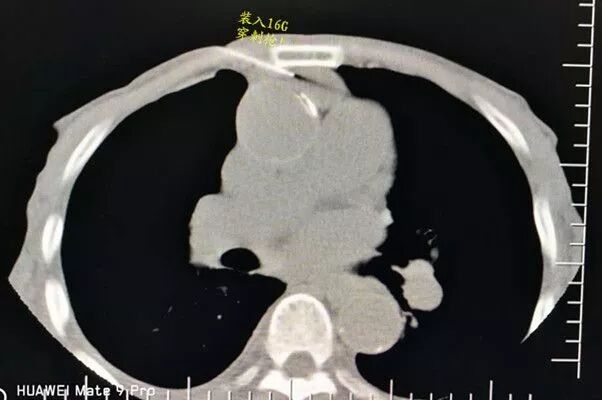

選擇右成角入路,穿越胸骨與主動脈間隙,該間隙僅僅10mm,并避開右胸廓內動脈,精細操作,先置入導針

再置入16G切割活檢槍,稍有偏差便可導致升主動脈損傷破裂,導致災難性后果發(fā)生。